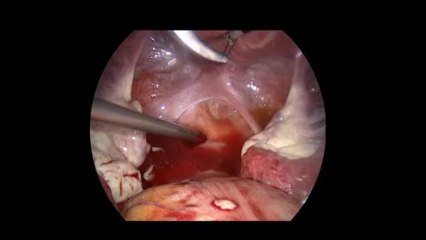

Diagnostik laparoskopi - Prof. Dr. Aydan Biri